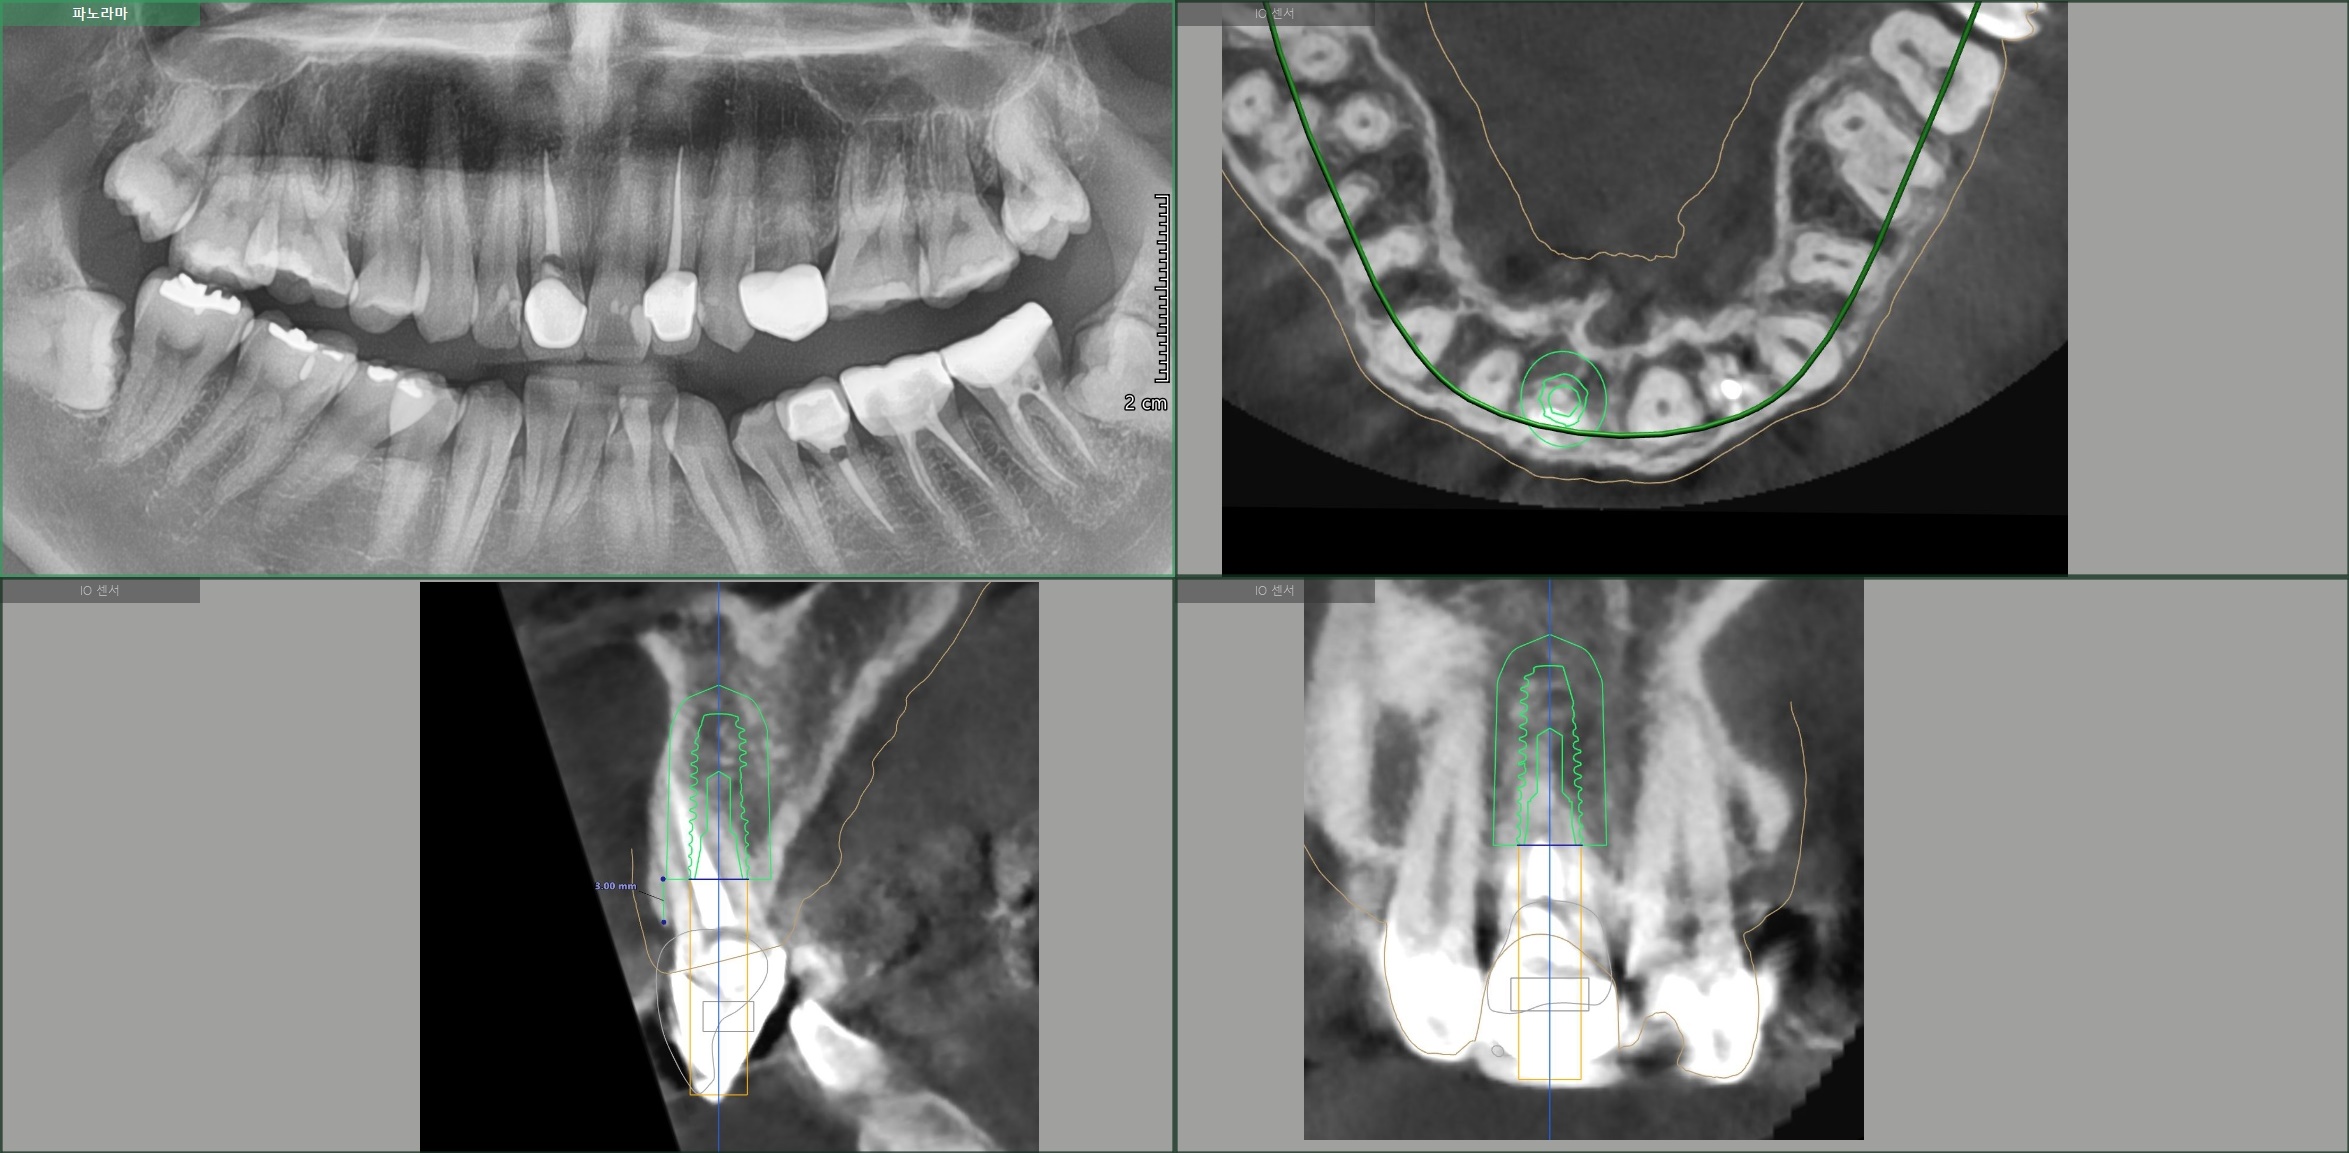

30대 남성분이 넘어져서 앞니가 흔들린다고 고촌치과에 내원하셨습니다.

CT 검사 결과 치아 머리 부분이 부러졌습니다.

살릴 수는 없는 상황이라 발치 즉시 임플란트와 즉시 임시치아를 계획하였습니다.

임플란트 식립후 임시치아를 바로 제작한 후 사진입니다.